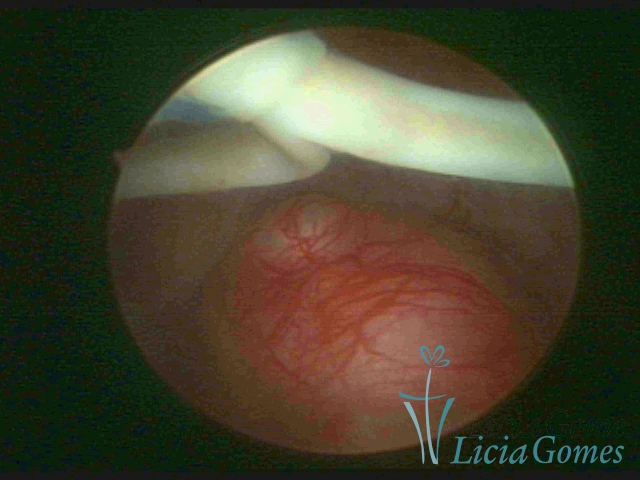

Mirena and myoma

×